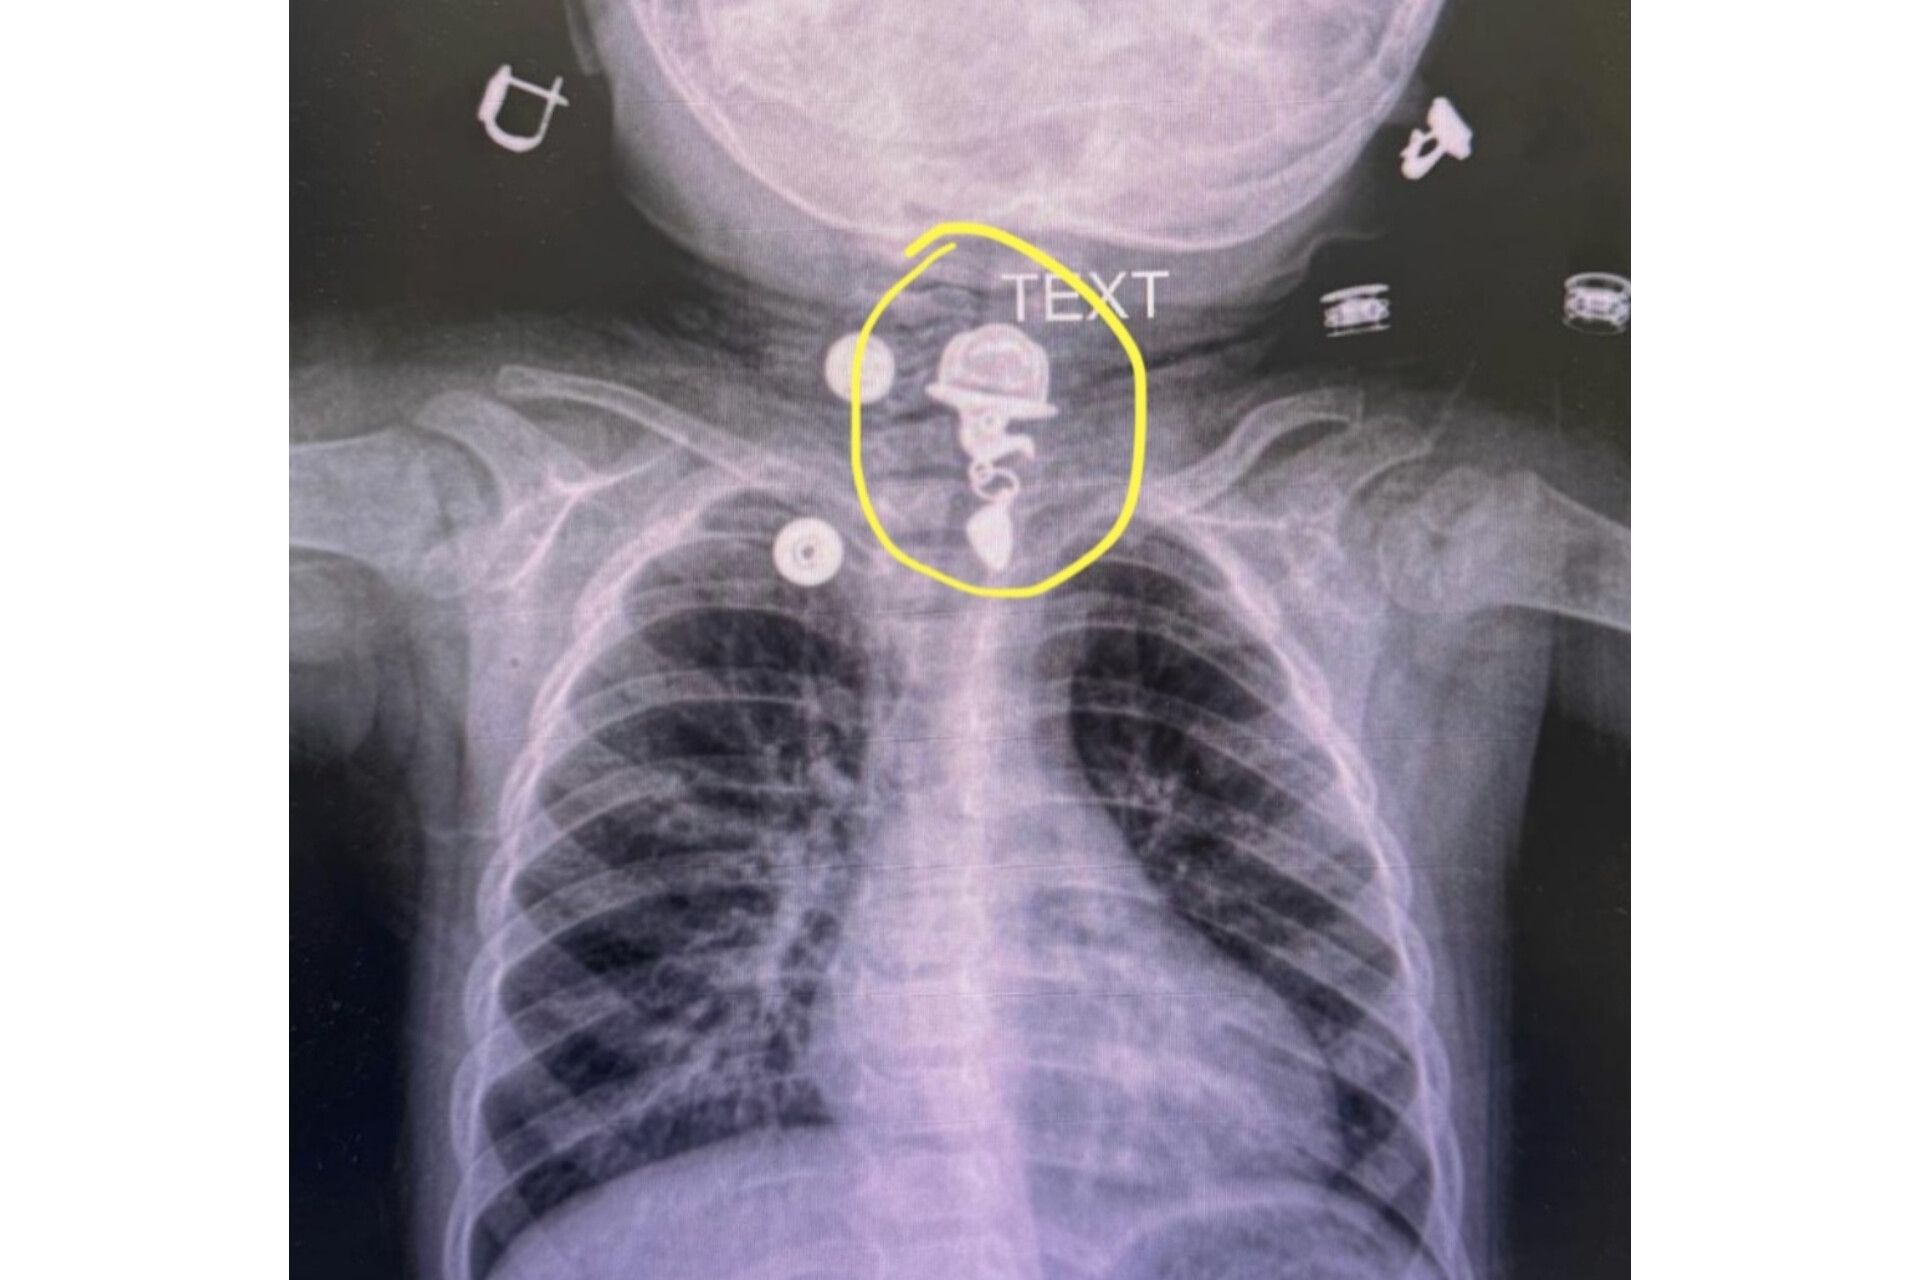

Türkiyədə 16 aylıq uşağın boğazında yad cism qalıb.

“Bu şəkildə mənə müraciət edən 16 aylıq uşaq xəstənin döş qəfəsinin rentgen görüntüsü göstərilir. İşarələdiyim sahədə qida borusunun yuxarı hissəsində metal boyunbağı ucu görünür. Təəssüf ki, uşaq ailəsinin xəbəri olmadan onu udub. Belə hallarda qida borusunda olan yad cisimlər mədə-bağırsaq tıxanmasına və ya perforasiyasına səbəb ola bilər. Eynilə, yad cisimlər traxeyaya daxil olduqda, qəfil tənəffüs çətinliyinə və tənəffüs dayanmasına səbəb ola bilər ki, bu da həyati təhlükə yaradan vəziyyətlərdir.